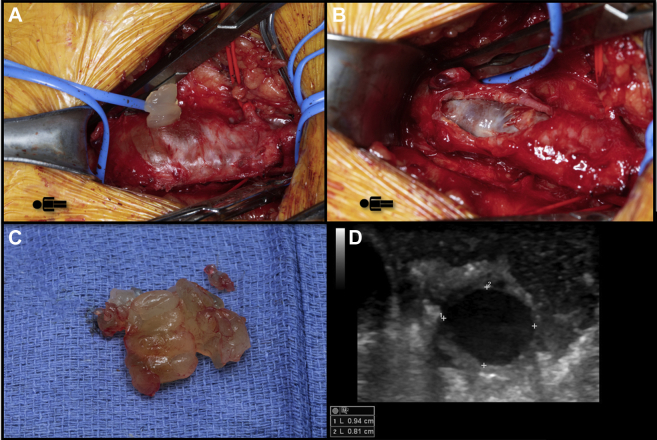

A shared decision was made for operative intervention owing to the risk of recurrent thrombosis. The patient underwent open right common femoral vein cyst excision (Fig 3, A-C) and ligation of the connection to the hip joint. Intraoperative ultrasound confirmed the normal caliber of the common femoral vein without compression at completion (Fig 3, D). Histopathologic examination of the specimen demonstrated features consistent with cystic adventitial disease. The patient had an uneventful postoperative course and was discharged to home on postoperative day 1. He continued taking rivaroxaban for 1 month, followed by a further 6 months of aspirin monotherapy. At the 4-month follow-up visit, his symptoms had completely resolved, and duplex ultrasound demonstrated no evidence of cyst recurrence.

Fig 3.

Intraoperative photographs of the adventitial cyst before (A) and after (B) cyst excision. C, Photograph of cyst contents. D, Select transverse view of the common femoral vein on intraoperative ultrasound demonstrating full expansion after cyst excision.